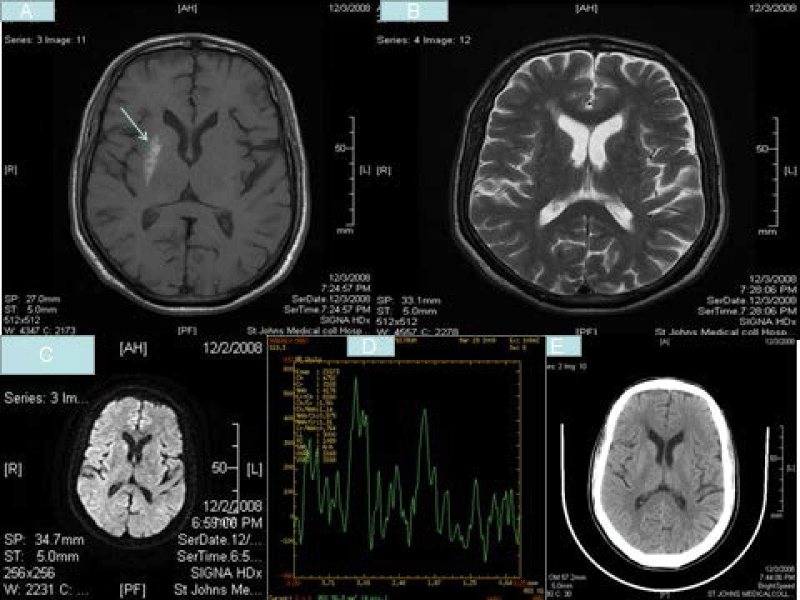

| Figure 1: T1W axial image (A) showing striatal hyperintensity(arrow),T2W axial images(B) showing hypointensity, Diffusion weighted images(C) showing no restriction, magentic resonance spectroscopy(D) showing reduced NAA peak and CT axial images(E) showing hyperdensity in striatum (MRI was done by General Electric HBX, 1.5 Telsa machine, 2007 model with 4.3 version software). |